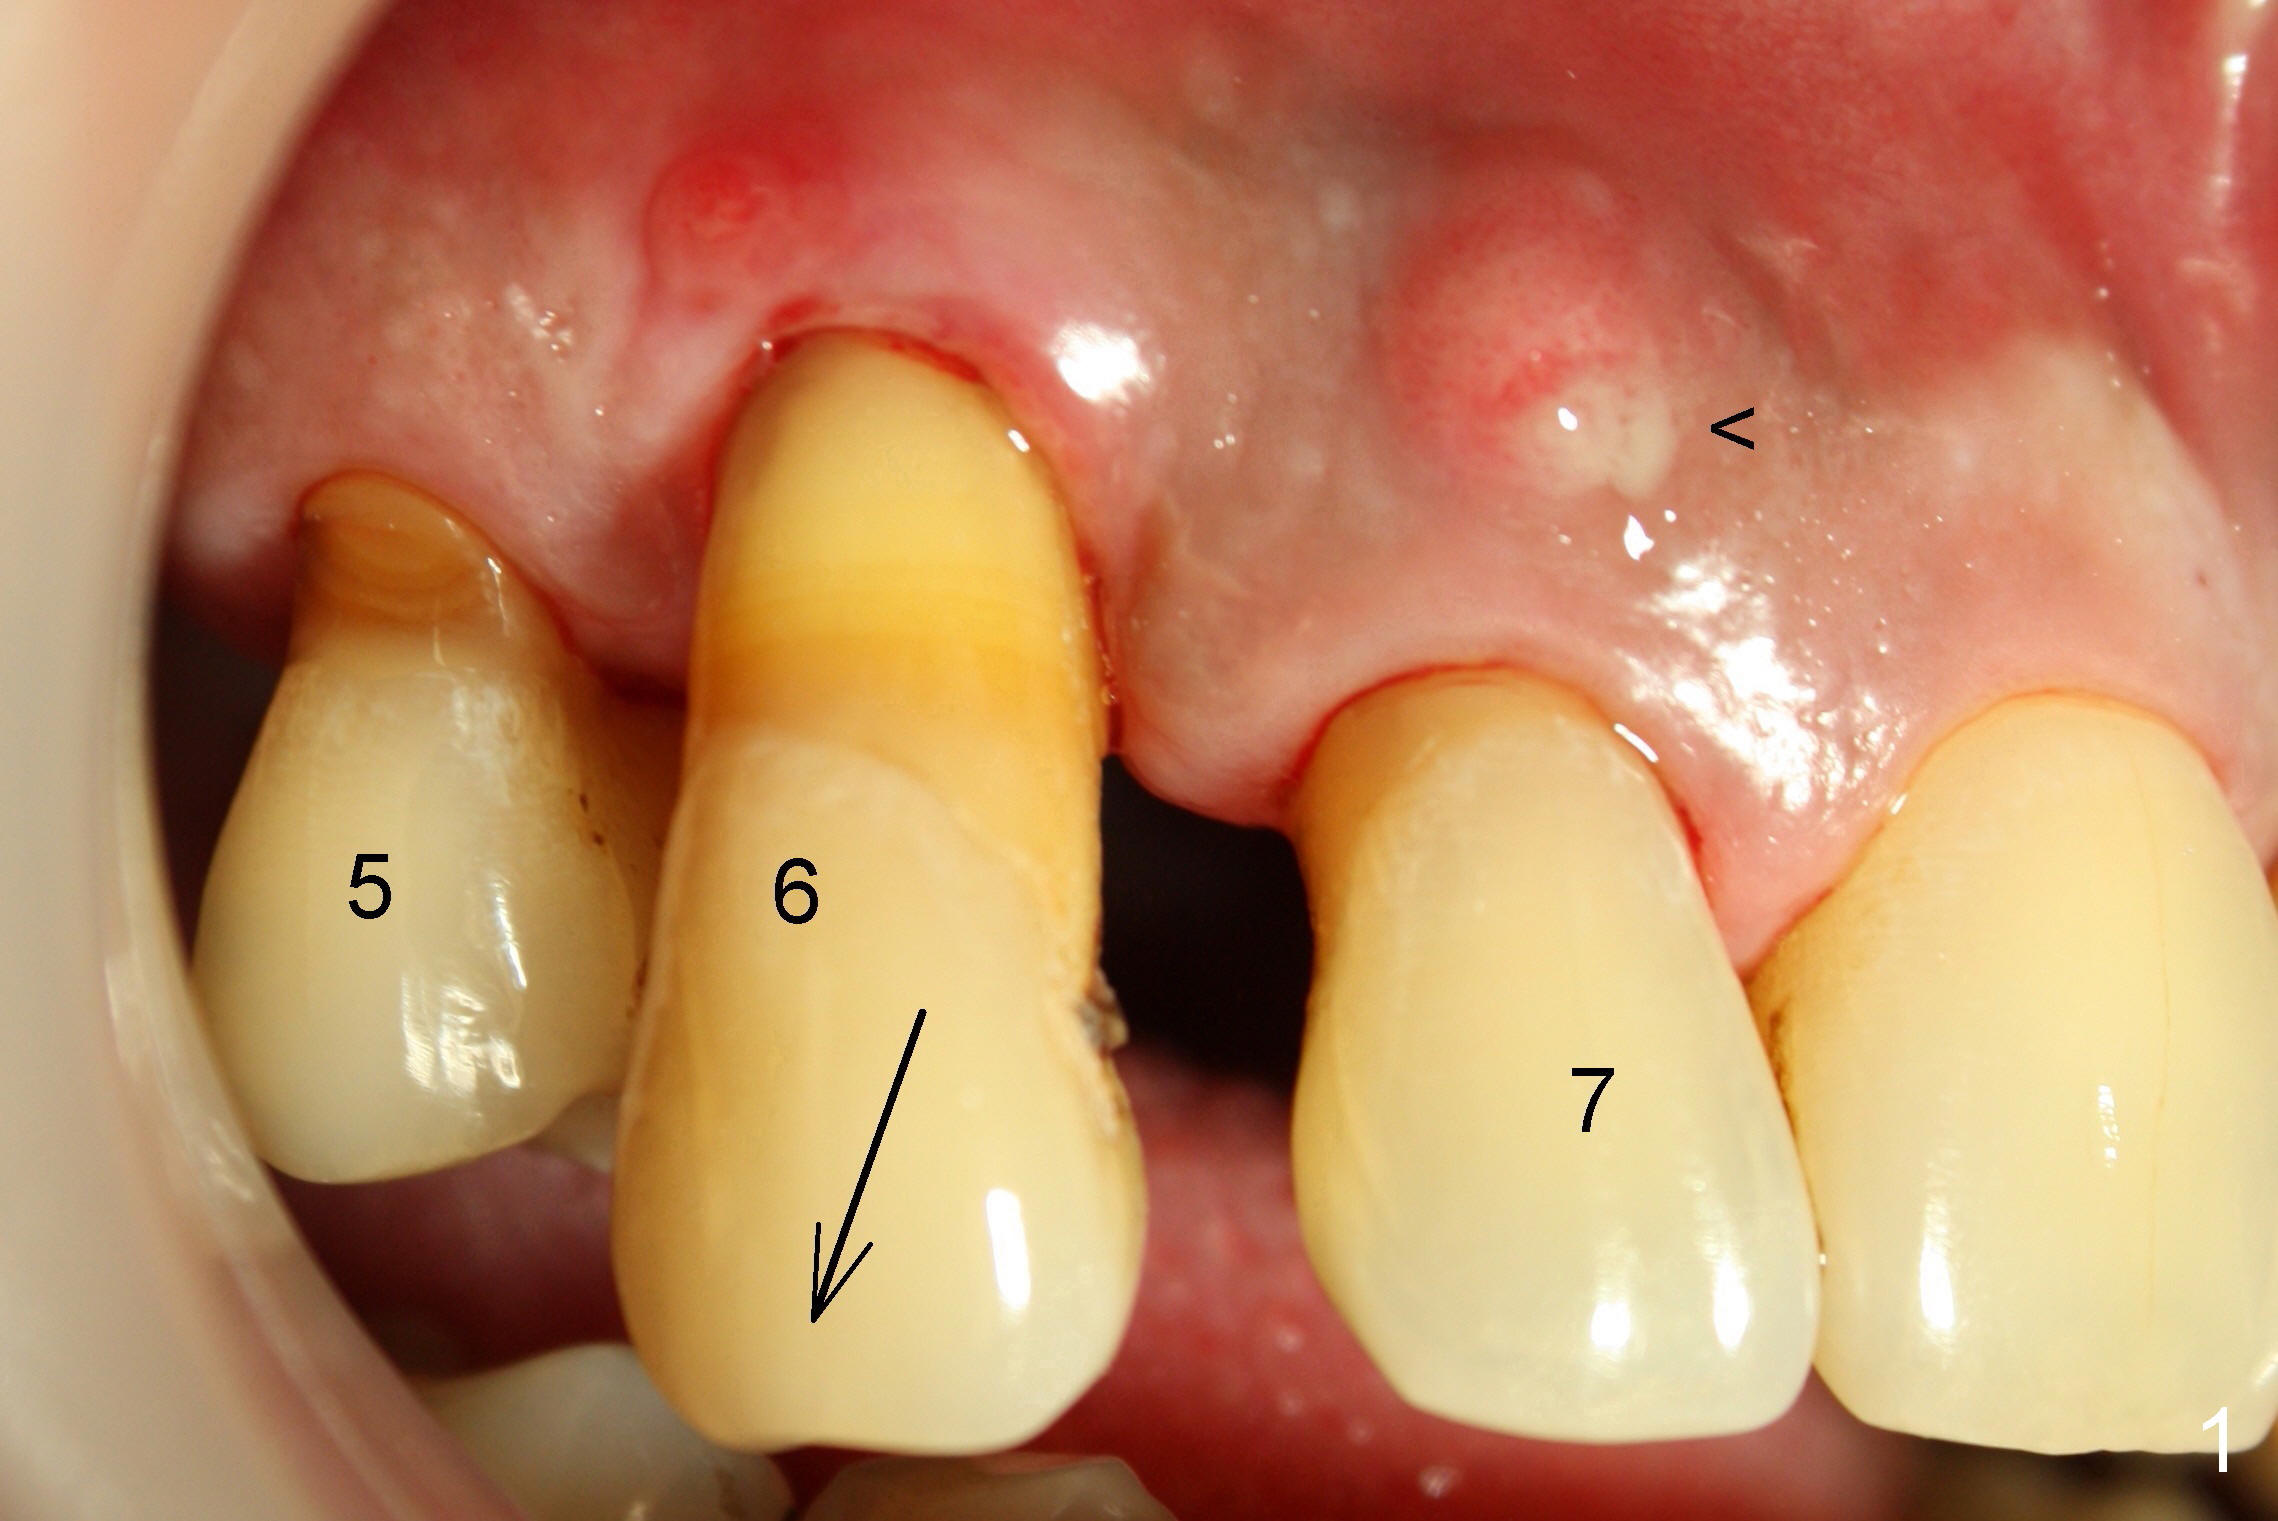

3. He has lost several upper teeth: #2,3,4,14 and 15.  The remaining teeth are loose, particularly #6,7, and 9 (Fig.1-4).  There are several treatment options for him.  Tell him that the doctor will discuss with him

6. Since the tooth # 6 shifts the most (Fig.1 arrow), it will be extracted first (the reason will be further explained in section #9), followed by thorough curettage, copious irrigation and soak with antibiotic